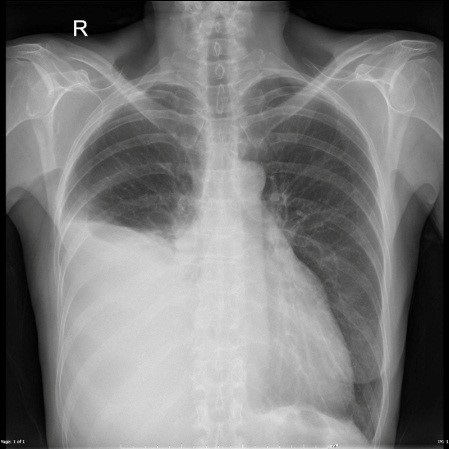

- X quang ngực thẳng là thăm dò đầu tay, phát hiện được dịch màng phổi khi lượng dịch > 150ml tùy thuộc vào mức độ

- TDMP là ít: mờ góc sườn hoành; trung bình: tạo đường cong damoiseau; nhiều: mờ toàn bộ trường phổi.